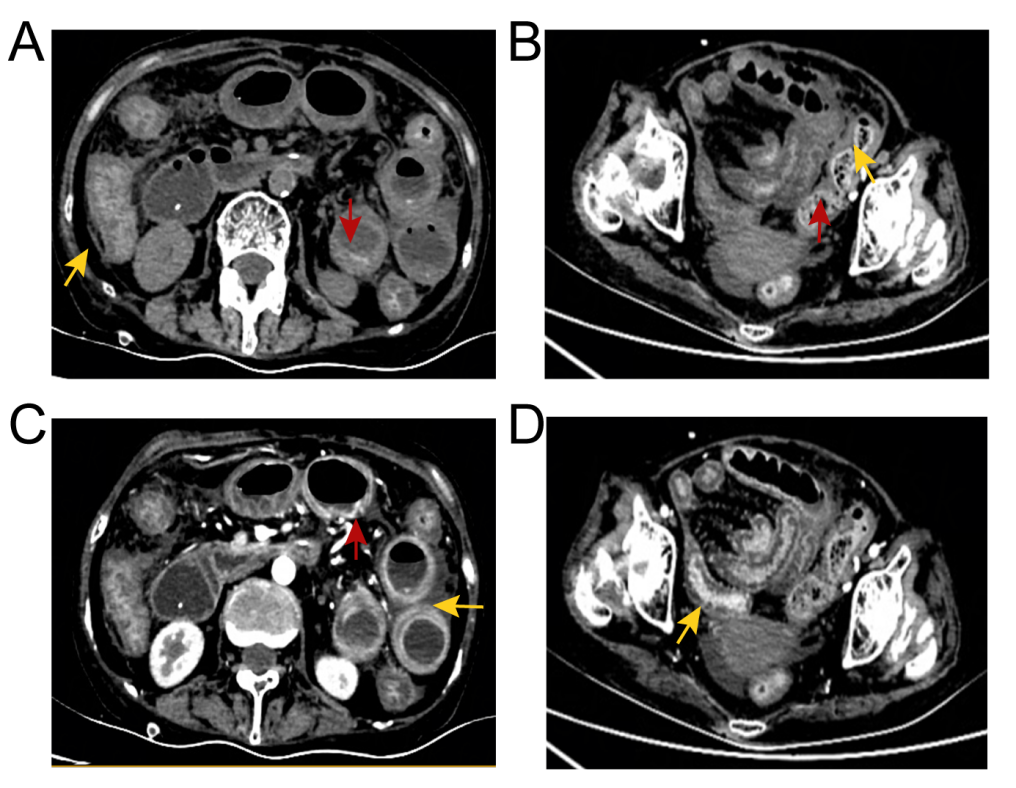

腹部计算机断层扫描的代表性图像。黄色箭头显示肠壁增厚和粘膜水肿;红色箭头显示黏膜充血;肠壁周围模糊的脂肪间隙表明腹腔积液。

腹部计算机断层扫描(CT)显示肝脏、胆囊、肾脏、胰腺、子宫和膀胱未见异样,但肠壁增厚,肠壁周围脂肪空间模糊,粘膜水肿,腹腔中存有大量腹水。于是,在超声引导下对患者行腹腔穿刺和腹水引流。腹水样本的抗酸染色、微生物培养(细菌和真菌)及细胞病理学结果均为阴性。